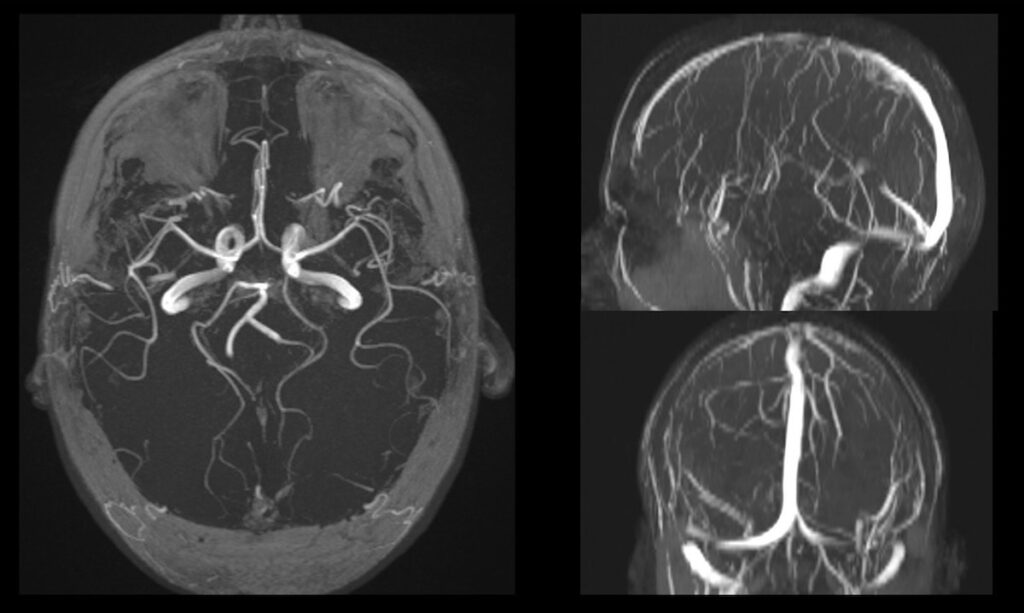

La questione di cosa si veda effettivamente in un supporto che archivia i dati di una risonanza magnetica ci conduce nel cuore di una mutazione ontologica dell’immagine contemporanea, dove la rappresentazione cessa di essere una mimesi dell’esterno per farsi trascrizione algoritmica della materia profonda. In un disco che registra tali dati, ciò che risiede non è un’immagine nel senso fotografico tradizionale – ovvero l’impronta di qualcosa del mondo su un supporto fotosensibile o dotato di memoria digitale – bensì un database di segnali a radiofrequenza, una sequenza di informazioni numeriche che descrivono il comportamento dei protoni all’interno di un campo magnetico. Questa architettura della memoria privata, prima di essere processata dal software, si presenta come un archivio di coordinate matematiche e intensità di segnale che mappano la struttura dei tessuti, la concentrazione d’acqua e i flussi ematici. L’immagine che alla fine appare sullo schermo e viene registrata in un disco è dunque una “traduzione”, una visualizzazione prodotta da una rete neurale, che trasforma la vibrazione molecolare in una topografia visibile del corpo umano.

L’osservatore che accede a questo disco si trova davanti a un’estensione algoritmica, dove la biografia clinica del soggetto è scomposta in una serie di sezioni assiali, coronali e sagittali: una stratificazione ipertestuale che permette di navigare all’interno della carne. Si vede qualcosa che rivela la vulnerabilità e la complessità della nostra struttura biologica, trasformando l’intimità organica in un riflesso esterno, condivisibile e consultabile. La grana di queste immagini è la traccia concreta di un’interazione tra la téchne e il vivente, dove il contrasto tra i bianchi e i neri definisce i confini di un’identità che non risiede più soltanto nella psiche, ma nella capacità della macchina di rendere navigabile l’invisibile.

DS: Esiste un’estetica delle immagini per il medico? Sì. Si tratta tuttavia di un’estetica “morale”, vale a dire intimamente connessa allo scopo dell’immagine, la rappresentazione di quella parte di corpo umano che mi accingo a valutare. Ancora direi che nel caso della risonanza magnetica (ma vale per qualsiasi metodica di diagnostica per immagini), ci si confronta con un’immagine attesa, quella data dalla memoria di tutte le immagini “normali”, cioè sane, accumulate nella mente con l’esperienza. Il “sano” è una perfezione attesa, tuttavia non geometrica, non ideale, fondata piuttosto sulla memoria delle immagini corrispondenti ad una “perfezione biologica”. Esiste comunque uno stupore per la qualità delle immagini, legato al dettaglio anatomico (“sembra una sezione anatomica” è una delle frasi più ricorrenti) o alla maggior evidenza delle anomalie (frutto di una maggior risoluzione di contrasto).

MZ: Esiste probabilmente un punto di rottura tra la necessità del referto e lo stupore della forma. In risonanza, i parametri T1, T2 o le sequenze pesate in diffusione cambiano radicalmente il contrasto e l’aspetto dei tessuti. Un artista può utilizzare questi “strumenti di contrasto” come se fossero filtri pittorici (o qualcosa del genere) e cosa può trovare o individuare nelle immagini registrate durante una risonanza magnetica?

DS: Certamente le scelte tecniche (immagini pesate in T1 o T2 o immagini in tecnica di diffusione) rispondono in momenti diversi dello stesso esame alla richiesta di risoluzione spaziale e risoluzione di contrasto. “Filtri pittorici” finalizzati direi. Detto questo direi che esiste un continuum senza soluzione fra estetica e finalità clinica. Anche in questo senso la medicina è un’arte, l’arte della cura, la cui via l’artista (in questo caso il medico) va cercando nelle immagini che con il tecnico e la macchina produce.